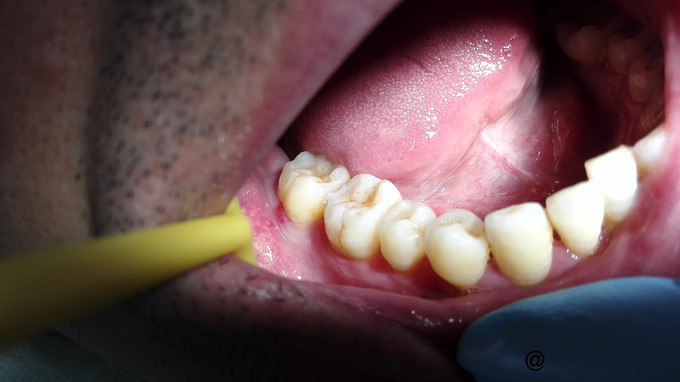

主诉:右下后牙咬合不适数天

检查:右下7牙冠完整,近龈缘可见一突起脓包,少量脓血分泌物溢出,PD=10mm,余位点PD=3mm左右,叩痛(+),松动I度,电活力测试较正常牙迟钝。X线示:右下7牙槽骨水平吸收至根中,根分歧下低密度影像,远中根管增宽,可以根折。复拍CT:右下7根分歧下低密度影像,未达根尖,两根在舌侧融合,唇侧分开,唇侧无根柱,未见根折。